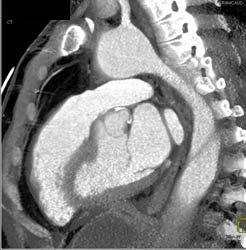

Aortic Dissection